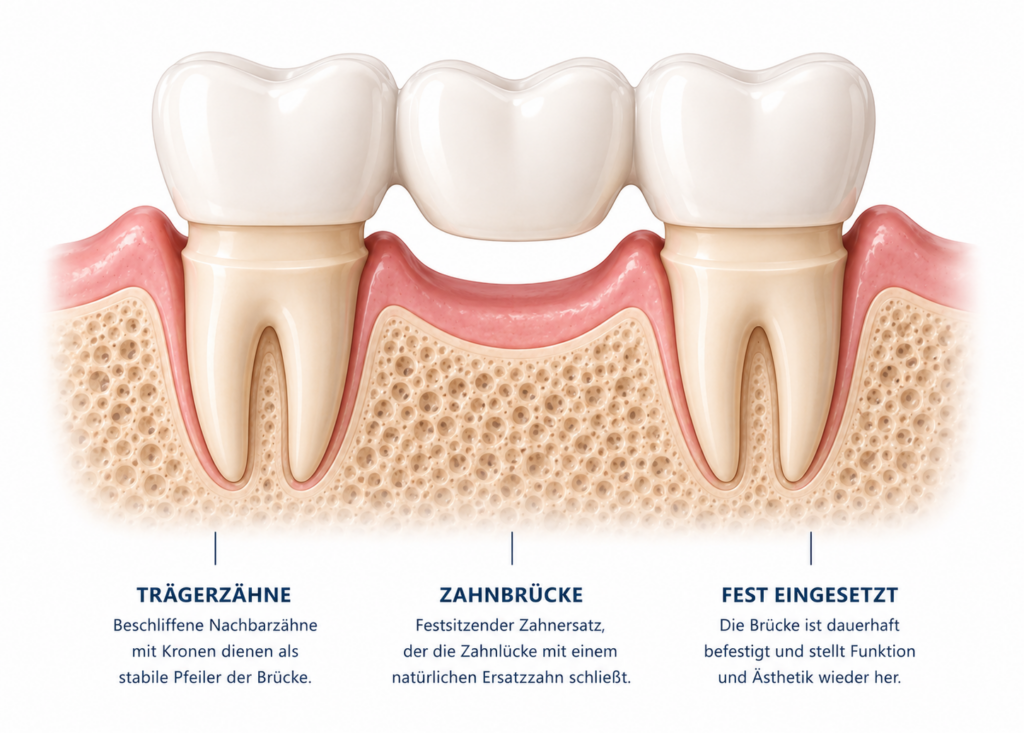

Festsitzender Zahnersatz wird dauerhaft im Mund befestigt und fühlt sich in der Regel am natürlichsten an. Dazu gehören zum Beispiel Kronen, die einen beschädigten Zahn stabilisieren, sowie Brücken, mit denen eine Zahnlücke geschlossen werden kann.

Wenn nur ein einzelner Zahn ersetzt werden muss, kann eine Krone oder eine Brücke infrage kommen. Fehlen mehrere Zähne, sind oft umfangreichere Lösungen notwendig – zum Beispiel herausnehmbarer Zahnersatz oder Zahnersatz auf Implantaten. Auch ästhetische Aspekte und der gewünschte Tragekomfort spielen eine wichtige Rolle.

Festsitzender Zahnersatz wie Kronen oder Brücken kann bei guter Pflege oft viele Jahre, teilweise sogar Jahrzehnte halten. Herausnehmbarer Zahnersatz hat in der Regel eine etwas kürzere Lebensdauer, da er stärker beansprucht wird und sich der Kiefer im Laufe der Zeit verändern kann.